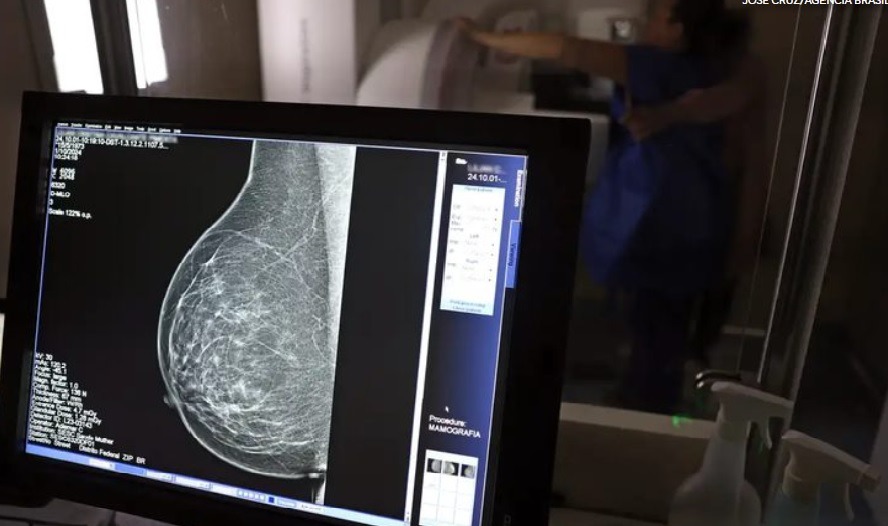

Ampliação de Mamografia

Recentemente o Ministério da Saúde anunciou mudança na faixa etária para realização da mamografia no SUS. A partir de agora o exame está disponível também para mulheres a partir dos 40 anos, mesmo na ausência de sintomas de câncer. A ampliação da faixa etária fortalece o diagnóstico precoce e o acesso à assistência, especialmente para mulheres que antes encontravam barreiras no sistema público de saúde, como a exigência de histórico familiar ou de sinais clínicos da doença. Em 2024, as mamografias realizadas em mulheres com menos de 50 anos já corresponderam a 30% do total, ultrapassando 1 milhão de exames.